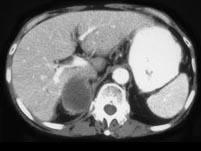

问题 男,75岁,右侧胸痛伴咯血3个月余,胸部CT提示右侧中央型肺癌,请结合图像,作出诊断 ( )

选项 A、右侧肾上腺癌 B、右侧肾上腺嗜铬细胞瘤 C、右侧肾上腺转移瘤 D、右侧肾上腺腺瘤 E、右侧肾上腺囊肿

答案 C